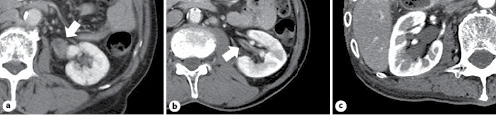

Table 1 shows the findings of the examination and management of 31 patients with atypical urinary cytology of the upper urinary tract. According to the initial CT findings in the upper urinary tract, we divided the patients into 4 groups: tumor-like lesions in 11 (Group A; Fig. 1a), wall thickening without tumor-like lesions in 8 (Group B; Fig. 1b), hydronephrosis without tumor-like lesions or wall thickening in 4 (Group C; Fig. 1c), and normal findings in 8 (Group D).

Classification based on the initial CT findings. Tumor-like lesions (arrow); Group A (a), wall thickening (arrow); Group B (b), hydronephrosis; Group C (c). CT, computed tomography.

In Group A, all 11 patients underwent nephroureterectomy and UTUC was confirmed histologically. Five patients had undergone nephroureterectomy immediately, without repeated RP, ureterorenoscopy, or biopsy. In Group B, UTUC was revealed in 3 of 8 patients and the remaining 5 patients were under surveillance without evidence of UTUC at the median follow-up period of 47 months (23–132 months). In Group C, UTUC developed in one of 4 patients; this patient was diagnosed with UTUC by nonscheduled RP following positive voided urinary cytology and appearance of tumor-like lesions in the ureter upon CT analysis. In Group D, UTUC was revealed in 2 of 8 patients. One positive patient had an extremely small tumor at the vesicoureteral junction that was revealed by ureterorenoscopy; this tumor was resected endoscopically. The other was diagnosed with carcinoma in situ of the upper urinary tract by repeated RP.